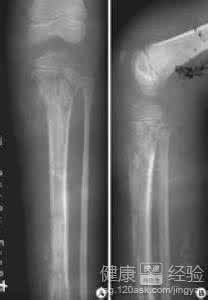

1、详细检查并详阅X线片,明确死骨及死腔位置,确定手术切口途径等。